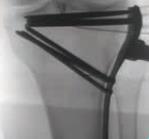

Proximal Tibia Fracture System

• The Proximal Tibia Fracture System is a comprehensive plating set designed for treatment of a variety of tibial plateau fractures.

• The system features three styles of Lateral Proximal Tibia Plates, a Medial Locking Plate, and a Posteromedial Buttress Plate to address intra-articular and extra-articular fractures of the proximal tibia.

• Streamlined and radiolucent instruments are designed to simplify the minimally invasive plating technique.